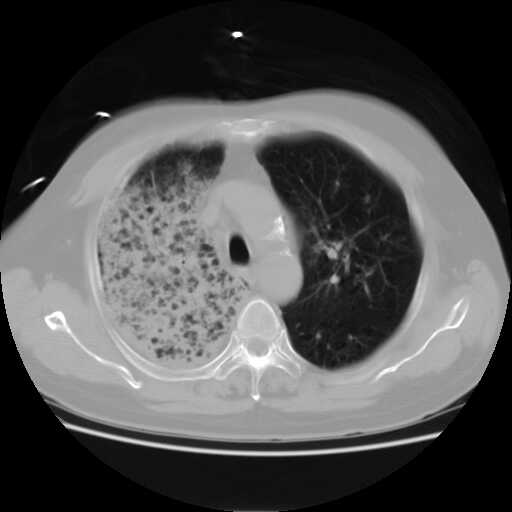

2008.8.17ct

病变从8.11-8.17明显改变,增多,以蜂窝状改变为主,类蜂窝肺,似弥漫性肺泡癌,但是病变进展太快,不符合弥漫性细支气管肺泡癌。因此考虑为特殊微生物感染,多以霉菌类常见,建议细菌微生物学检查。

疑点二:影象表现怪异,大片阴影内见多发筛孔征,如何解释.

结合临床慢支炎肺气肿,肺心病病史,三次胸片观察可见病情发展变化迅速,病情凶险,考虑多重感染伴ards.